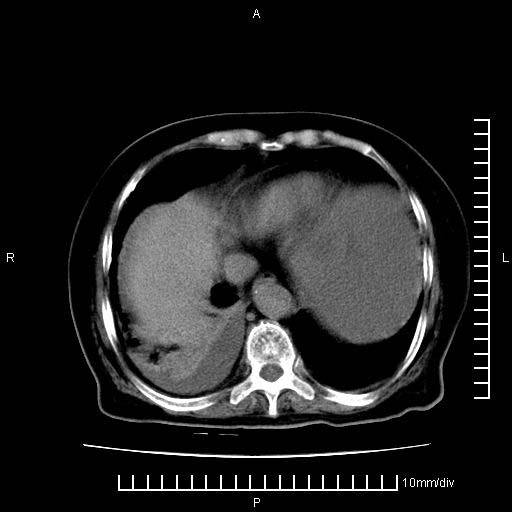

标题: CT28280:腹部增强:女性,80岁

上腹疼痛月余,外院核磁诊断胰腺癌。现临床示右下腹可明显触及包块,可片子上怎么没有看到?

1。胰腺ca伴腹膜腔转移

2。肝左叶低密度灶,考虑转移可能

支持胰腺癌肝内转移,腹水改变。

1、考虑胰腺癌伴腹膜腔转移,胸腹水。

2、肝脏转移可能。

1)考虑胰腺癌并胰腺假性囊肿形成。2)肝内低密度灶,不排除转移。3)右肾盂积水。4)腹水。5)右侧胸腔积液并右肺下叶部分膨胀不全。

考虑胰腺ca伴腹膜腔转移、肝左叶转移、右肾积水。右胸腔积液。